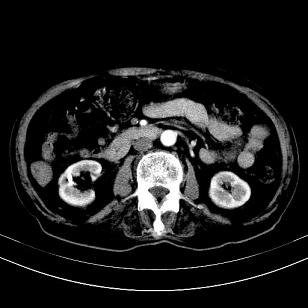

来源-右侧肾上腺。

考虑右侧肾上腺巨大占位;恶性?

另:右肾结识,多发小囊肿。

考虑右侧肾上腺肿瘤并肝内多发转移。右侧肾上腺呈“八”字形,包括内侧枝及外侧枝,内侧枝受压,考虑外侧枝原发肿瘤。”

考虑肝右后叶肝癌(部分外生)伴肝内多发性转移;不排除右侧肾上腺区恶性嗜铬细胞瘤并肝转移。